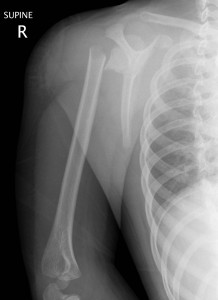

Above: Complete fracture of shaft of humerus with mild displacement

Above: Spiral fracture of shaft of humerus